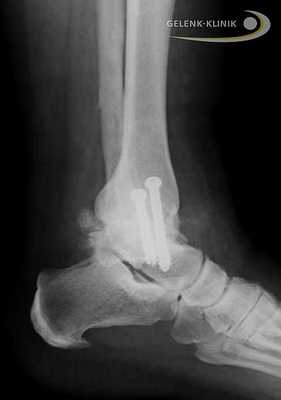

Рентген после корригирующей операции пяточной кости. Остеотомия деформированной кости может восстановить линию нагрузки нижней конечности. © Gelenk-Klinik

Прочное важное для остеосинтеза костное соединение, закрепляется при помощи винтов либо пластин. Артроскопические вмешательства подразумевают лишь микроскопические разрезы на коже. Сохранение мягких тканей является является важным элементов в таком лечении: только при низком рубцевании, в будущем возможно эндопротезирование.

Артродез голеностопного сустава проводится и при использовании интрамедуллярных гвоздей, которые соединяют большеберцовую кость с таранной и пяточной. Артроз нижнего голеностопа и тяжелые травмы пяточной кости требуют проведения данной методики. Применение интрамедуллярных гвоздей для обездвиживания голеностопа приводит ещё и обездвиживанию сустава между пяточной и таранной костью. © Gelenk-Klinik